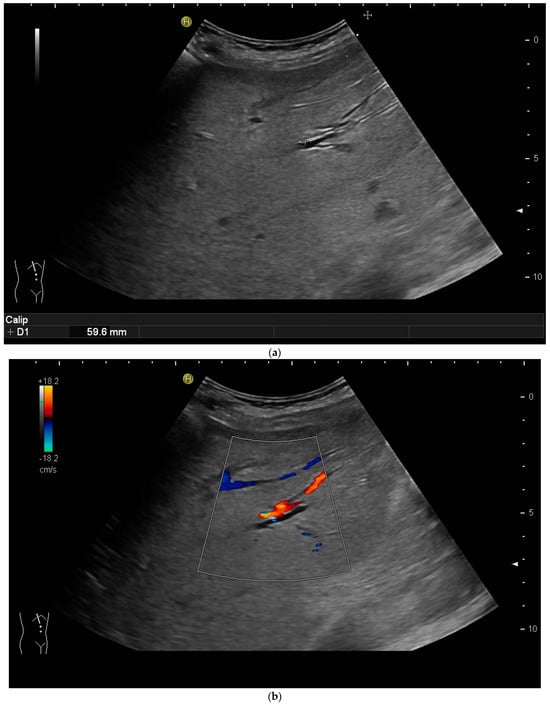

Most authors recommend a transhepatic approach in order to prevent biliary leakage to the abdominal cavity during drainage or after removal of drainage [43,55,56,76,77] (Figure 9).

Figure 9.

(a) Transhepatic puncture of an inflamed gall bladder in the in-plane technique. The Chiba needle is depicted well; (b) A few days later, laparoscopic cholecystectomy was performed. The drainage ran through Segment V of the liver. It was removed without provoking biliary leakage from the liver parenchyma.

The consideration is that a perforation in the hepatic surface of the gallbladder will be covered by the liver tissue after the removal of the drain. However, retrospective analyses comparing the transhepatic route with the transperitoneal (i.e., nontranshepatic) access (Figure 10) report no differences in the complication rates [58,78,79].

Figure 10.

PGBD without passing the liver and using the trocar technique: straightened drainage passes right below the lower liver margin into the gallbladder.

Again, the “in plane” approach is recommended to depict the needle in real time and continuously on its way. This is mandatory because iatrogenic perforation of the posterior gallbladder wall must be avoided. Both the drainage techniques, Seldinger (Figure 11a–c) and trocar (direct puncture, cf. Figure 10), may be used, depending on the physician’s preferences [43,58].